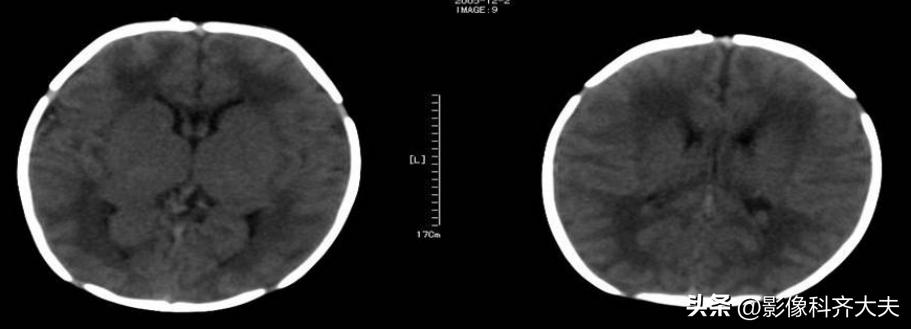

对于以下正常新生儿颅内高密度,CT容易误诊为出血

(1)正常新生儿横窦和乙状窦可呈条状密度增高影,易误为枕部硬膜下血肿或蛛网膜下腔出血。

(2)正常新生儿,直窦及纵裂池区CT可表现为线状略高密度区。当蛛血时,此区密度增高,宽度增加,且宽窄不一,可呈前宽后窄或前窄后宽及不规则形。其宽度≥5mm,可确诊为新生儿蛛血。

(3)正常新生儿的上矢状窦区CT表现为三角形高密度,密度均匀、边缘锐利,且无张力。新生儿蛛血时,此区边缘欠规整及张力升高,且其中心区可呈略低密度改变,是由于此区有新鲜出血与局部静脉窦有密度差值所致——空三角征。此为诊断该区蛛血的重要征象。